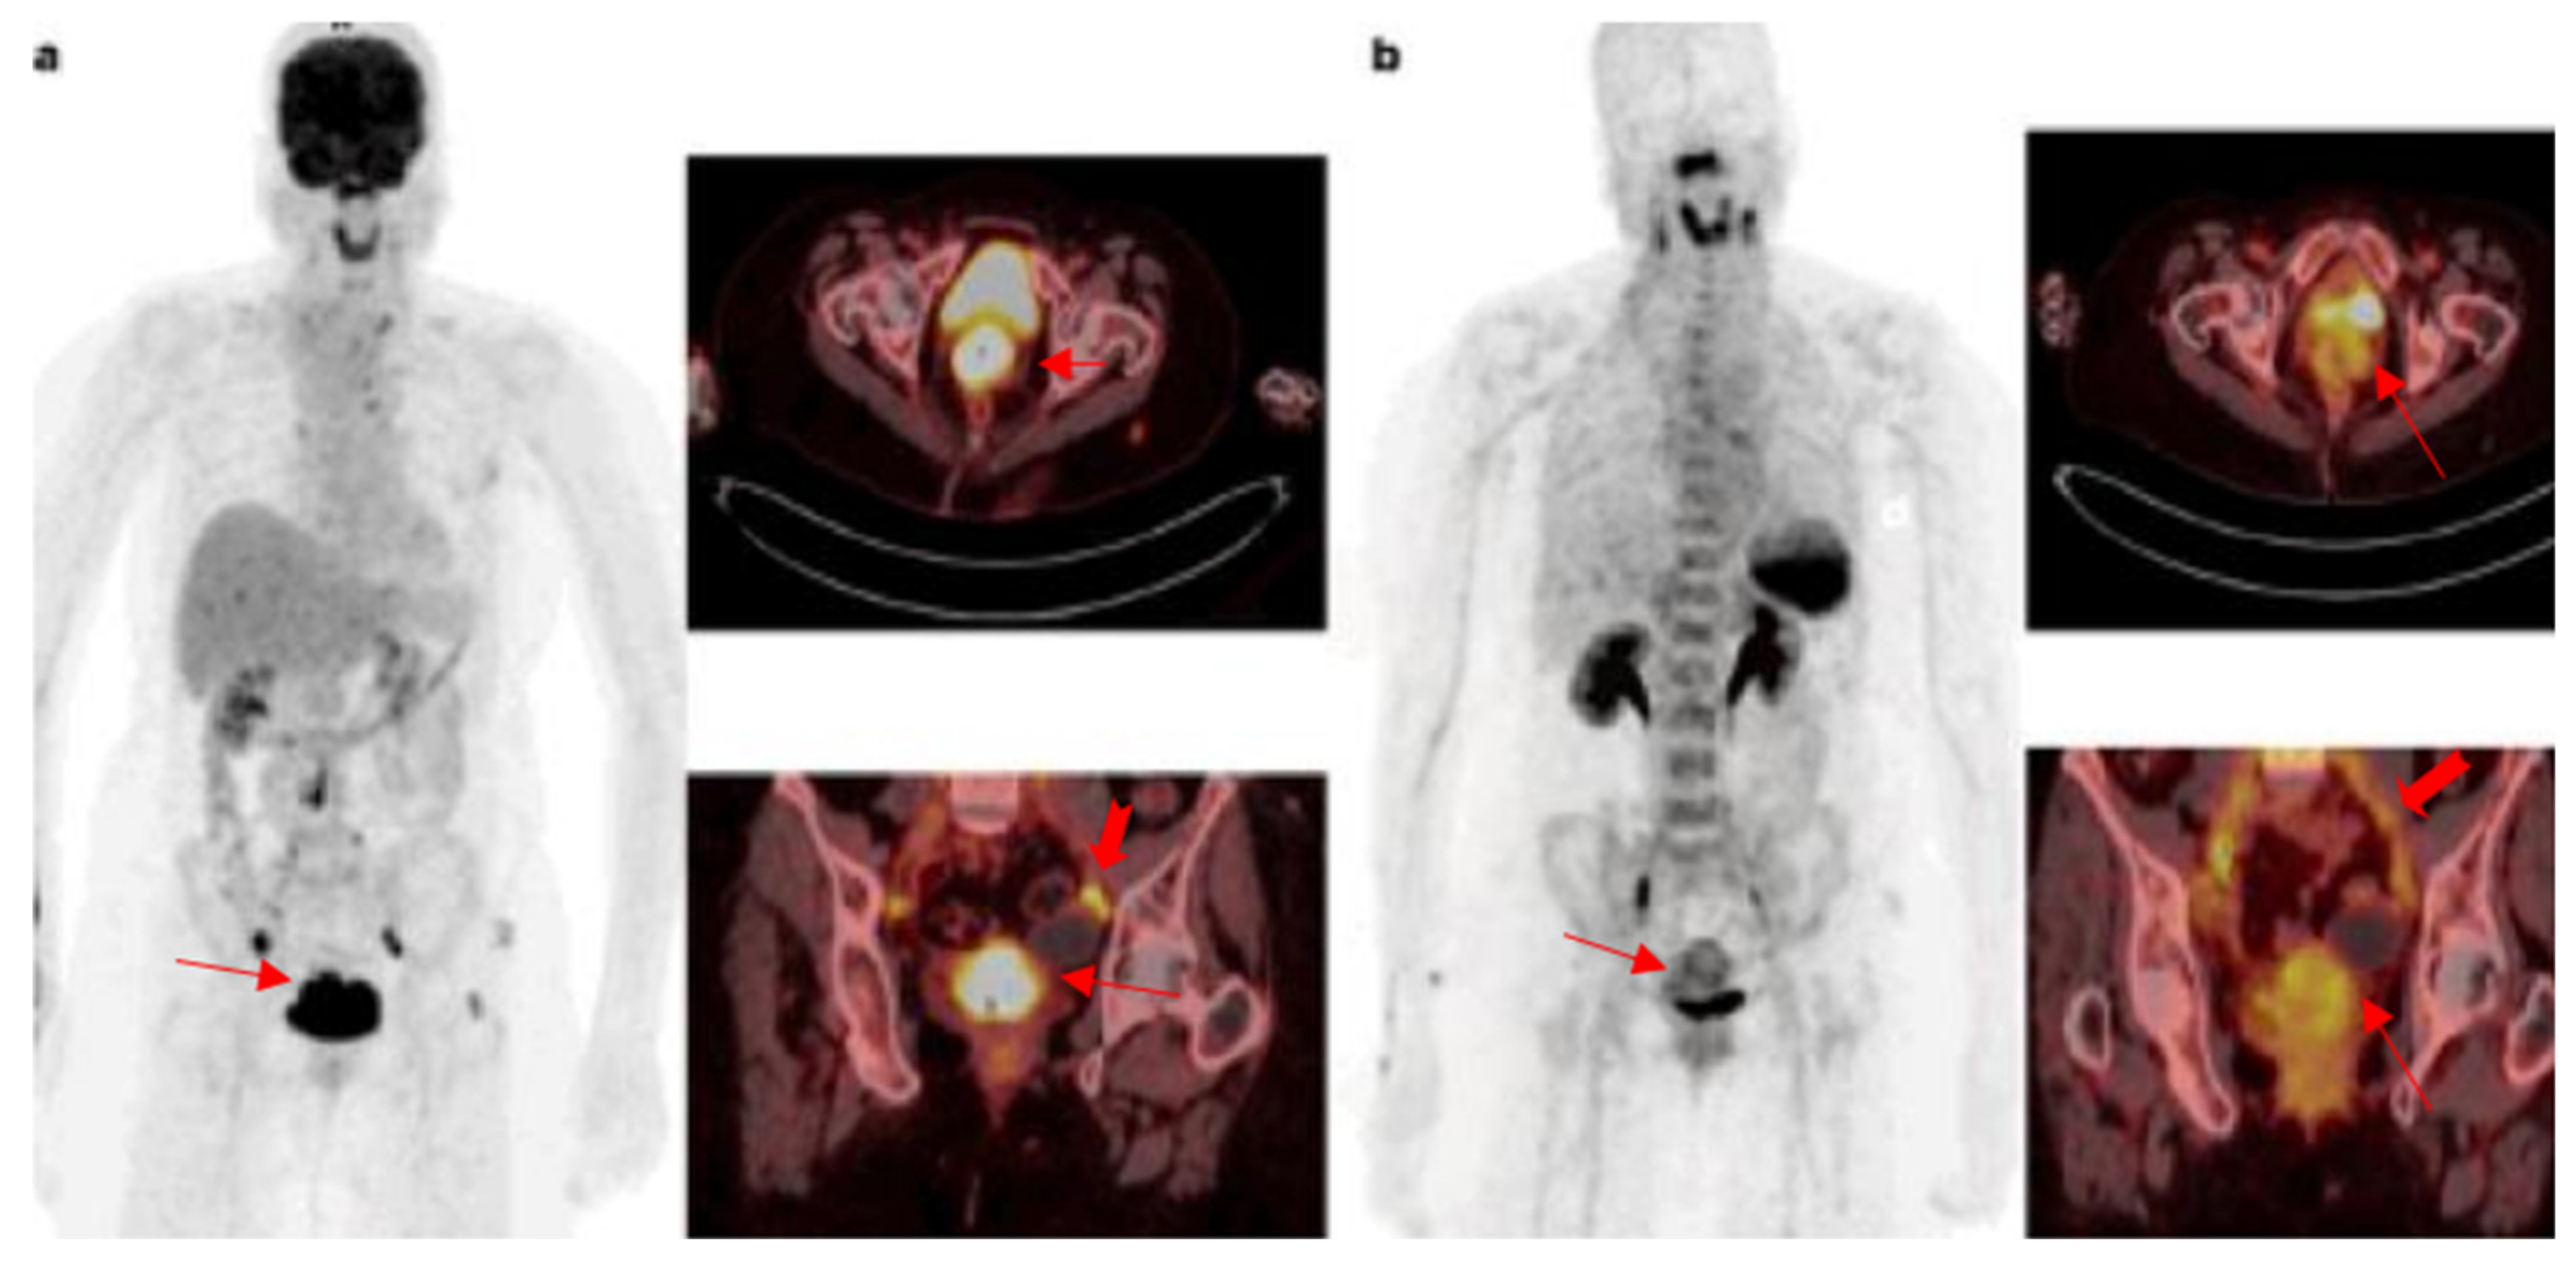

- Bluemel, C.; Hahner, S.; Heinze, B.; Fassnacht, M.; Kroiss, M.; Bley, T.A.; Wester, H.-J.; Kropf, S.; Lapa, C.; Schirbel, A. Investigating the chemokine receptor 4 as potential theranostic target in adrenocortical cancer patients. Clin. Nucl. Med. 2017, 42, e29–e34. [Google Scholar] [CrossRef]

- Werner, R.A.; Kircher, S.; Higuchi, T.; Kircher, M.; Schirbel, A.; Wester, H.J.; Buck, A.K.; Pomper, M.G.; Rowe, S.P.; Lapa, C. CXCR4-Directed Imaging in Solid Tumors. Front. Oncol. 2019, 9, 770. [Google Scholar] [CrossRef]